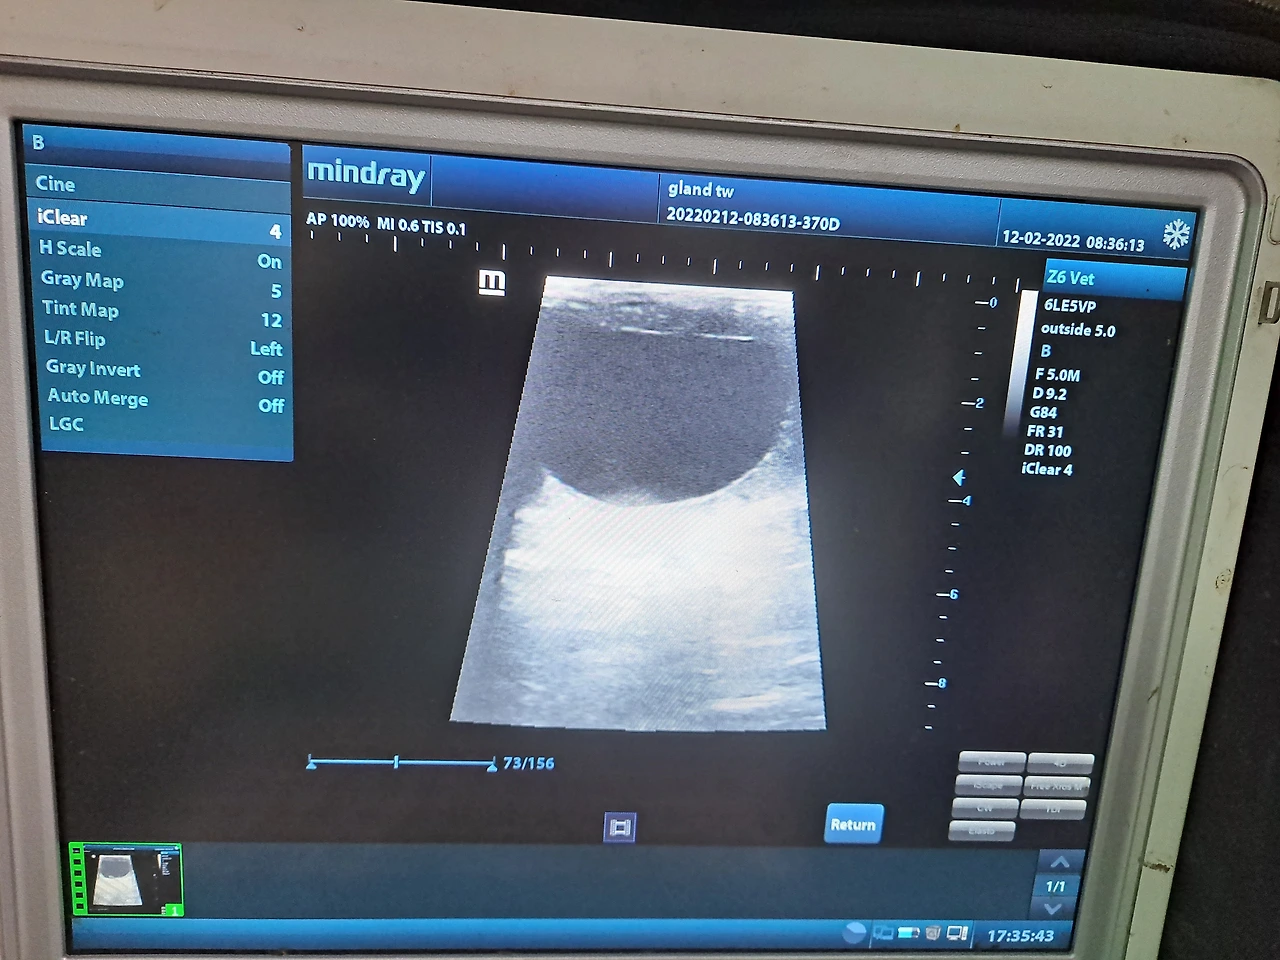

*사진은 번식 초음파 검사 모습과 배란이 임박한 난포의 초음파 모습입니다.

그러면 수의사는 교배일을 어떻게 선택하는가. 보통은 번식농가를 이틀에 한 번씩 방문하여 직장 초음파 검사를 통해서 씨암말 난소와 자궁 상태를 관찰한다. 그래서 난소 내 난포가 점점 커가면서 배란일이 다가오면 씨수말과 만나는 날을 정한다. 교배 후 자궁으로 들어간 정자는 난관에 이르러서 난자가 내려오기를 기다린다. 이때 정자가 수정되기 전까지 혼자서 살아남을 수 있는 시간을 3일에서 5일 정도까지로 보지만, 보통은 이틀 내에 난자와 만나야 수정 가능성이 높다고 생각한다. 그러므로 수의사는 교배하고 이틀 후에 난소를 다시 확인해서 배란 여부를 체크한다.

수의사는 배란일을 맞추기 위해서 여러 가지 데이터를 이용한다. 난포의 크기와 촉감, 씨암말 배란주기, 자궁의 주름이나 감도까지 여러 가지 정보를 종합하여 합방일을 택일한다. 하지만, 씨암말은 기계가 아니라 생명체이기 때문에 변수가 많다. 따라서 배란일을 정확히 맞추는 일은 매우 어렵다. 슈퍼컴퓨터로도 예측할 수가 없는 것이 여자의 마음이라는데, 그 많은 사모님 말들이 언제 만남을 원하는지 어찌 정확하게 집어내겠는가. 그저 종부의 결과가 좋을 것 같은 확률 높은 날을 고를 뿐이다.